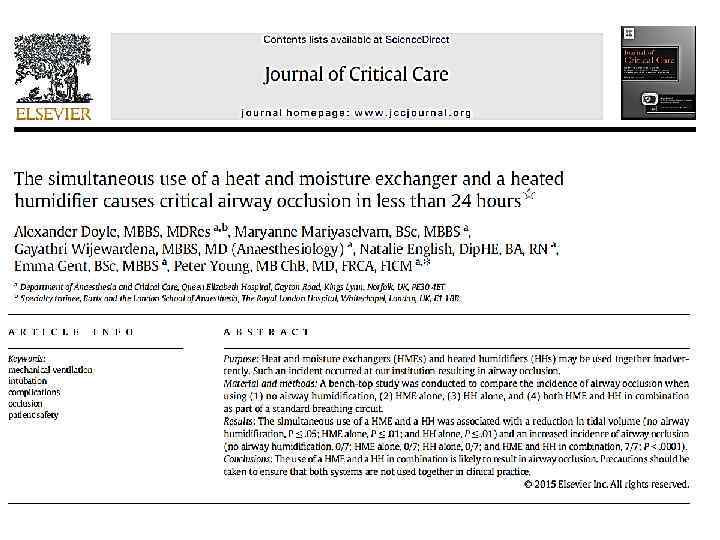

ТВО и увлажнитель

ТВО и увлажнитель